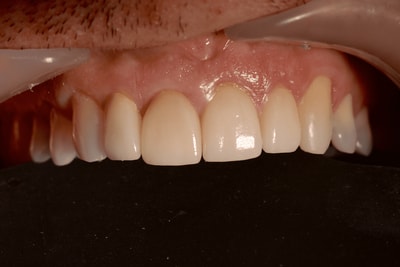

Cas numero 2 :

Cas terminé